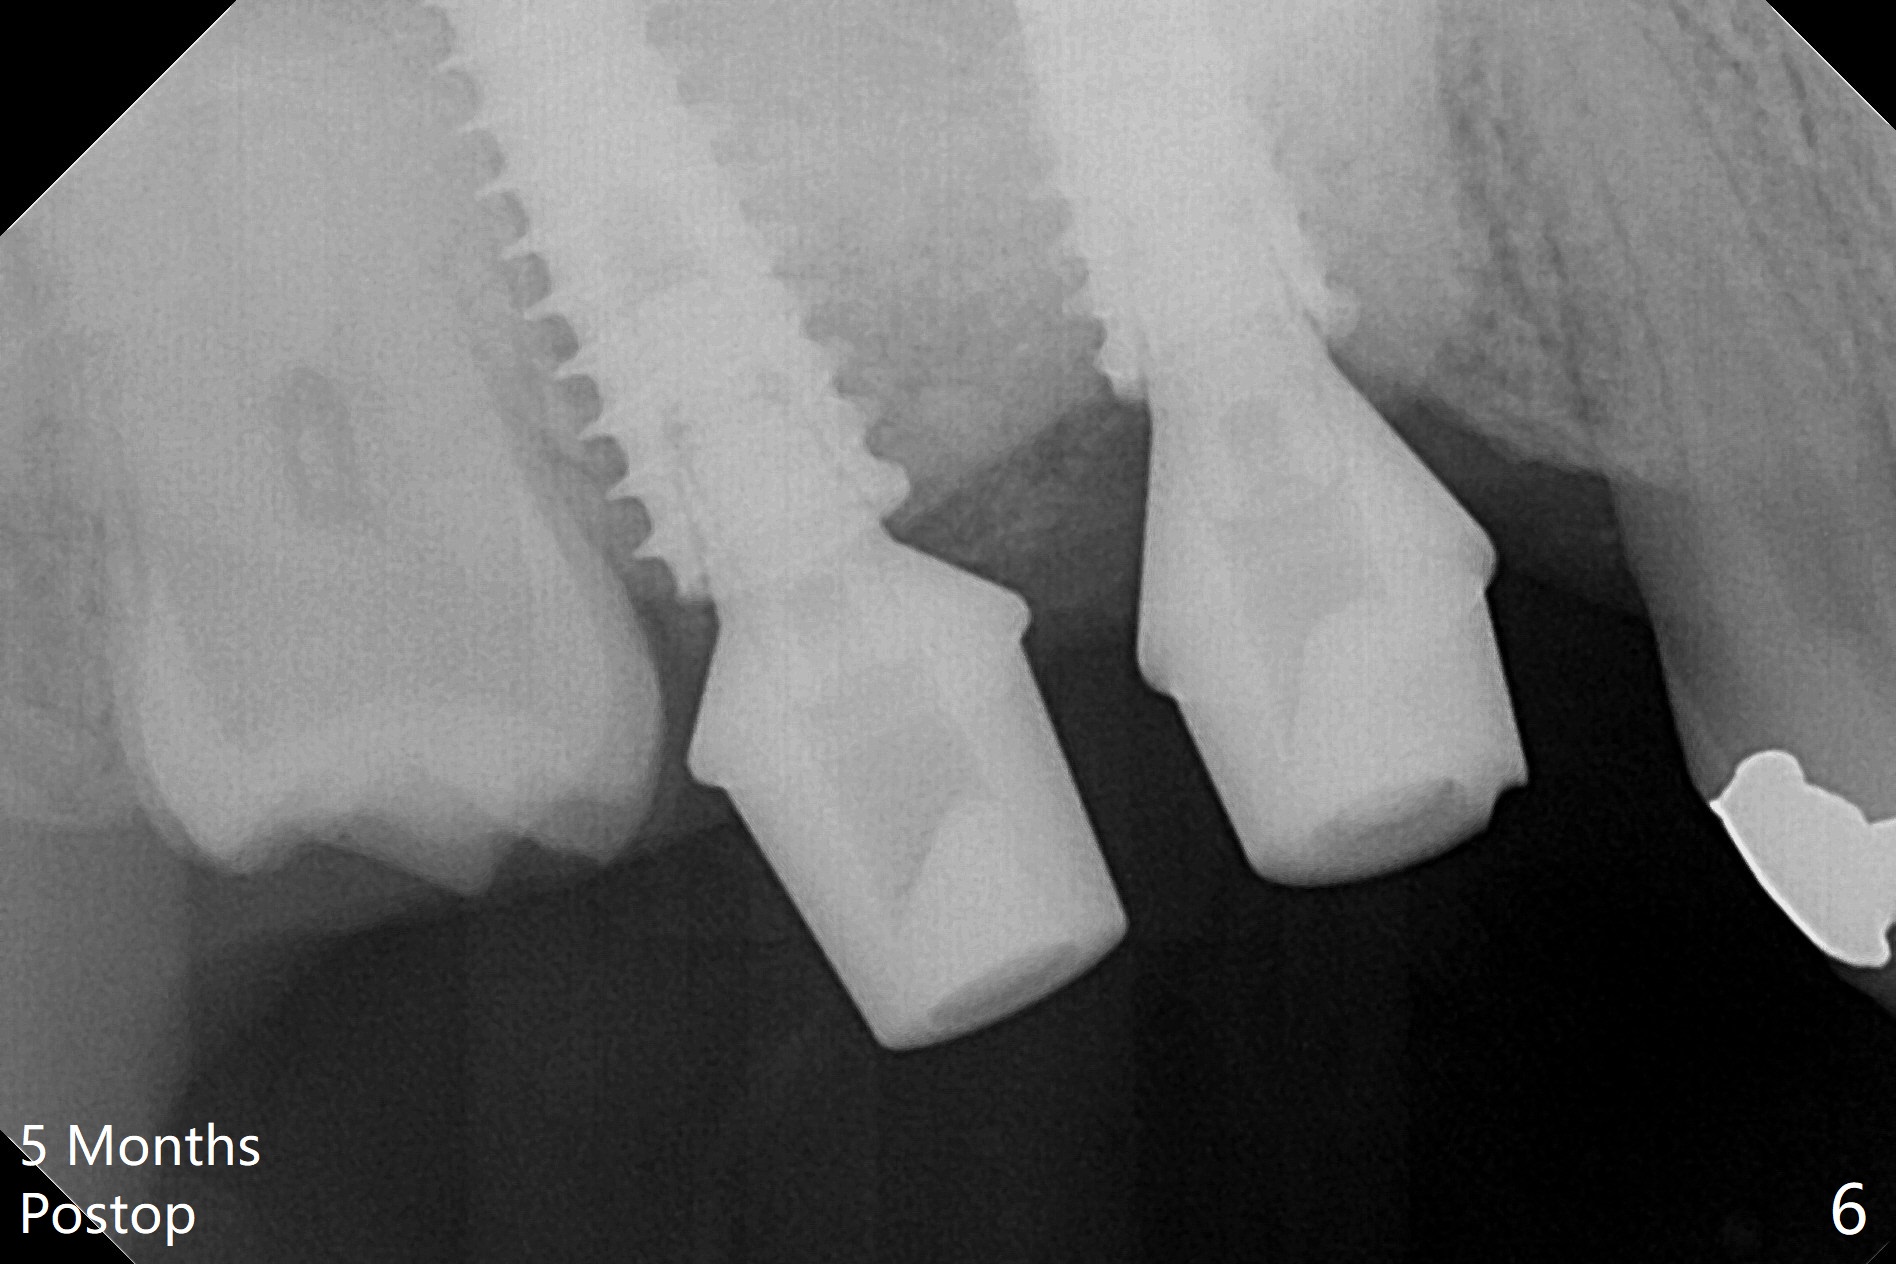

The gingiva at #2 adapts to the abutment 3.5 months post placement (Fig.1). After incision, osteotomy at #3 is initiated by free hand, which is found off (Fig.2 (red line: normal trajectory)). After repositioning osteotomy, a 4.5x11 mm dummy implant is placed with minor trajectory issue (Fig.3). Following further adjustment, a 5x11 mm implant is placed with relatively normal axis; a 6.5x4(4) mm abutment is inserted. Autogenous bone, Vanilla and Osteogen are placed distobuccally (Fig.4). Guided surgery should be more efficient and precise. There is no implant thread exposure 9 and 5 months postop at #2 and 3, respectively (Fig.5,6). The mesial wall of the crown at #2 is thin, having a crack line. The crowns at #2 and 3 are cemented with RelyX Ultimate Adhesive Resin Cement bonding. If the crown fractures, change the abutment (6.5x5.7(2) mm) to the one with smaller diameter (4.5 or 5.0 mm), or trim the abutment mesially heavily. Guided surgery or stent should prevent the potential complication.